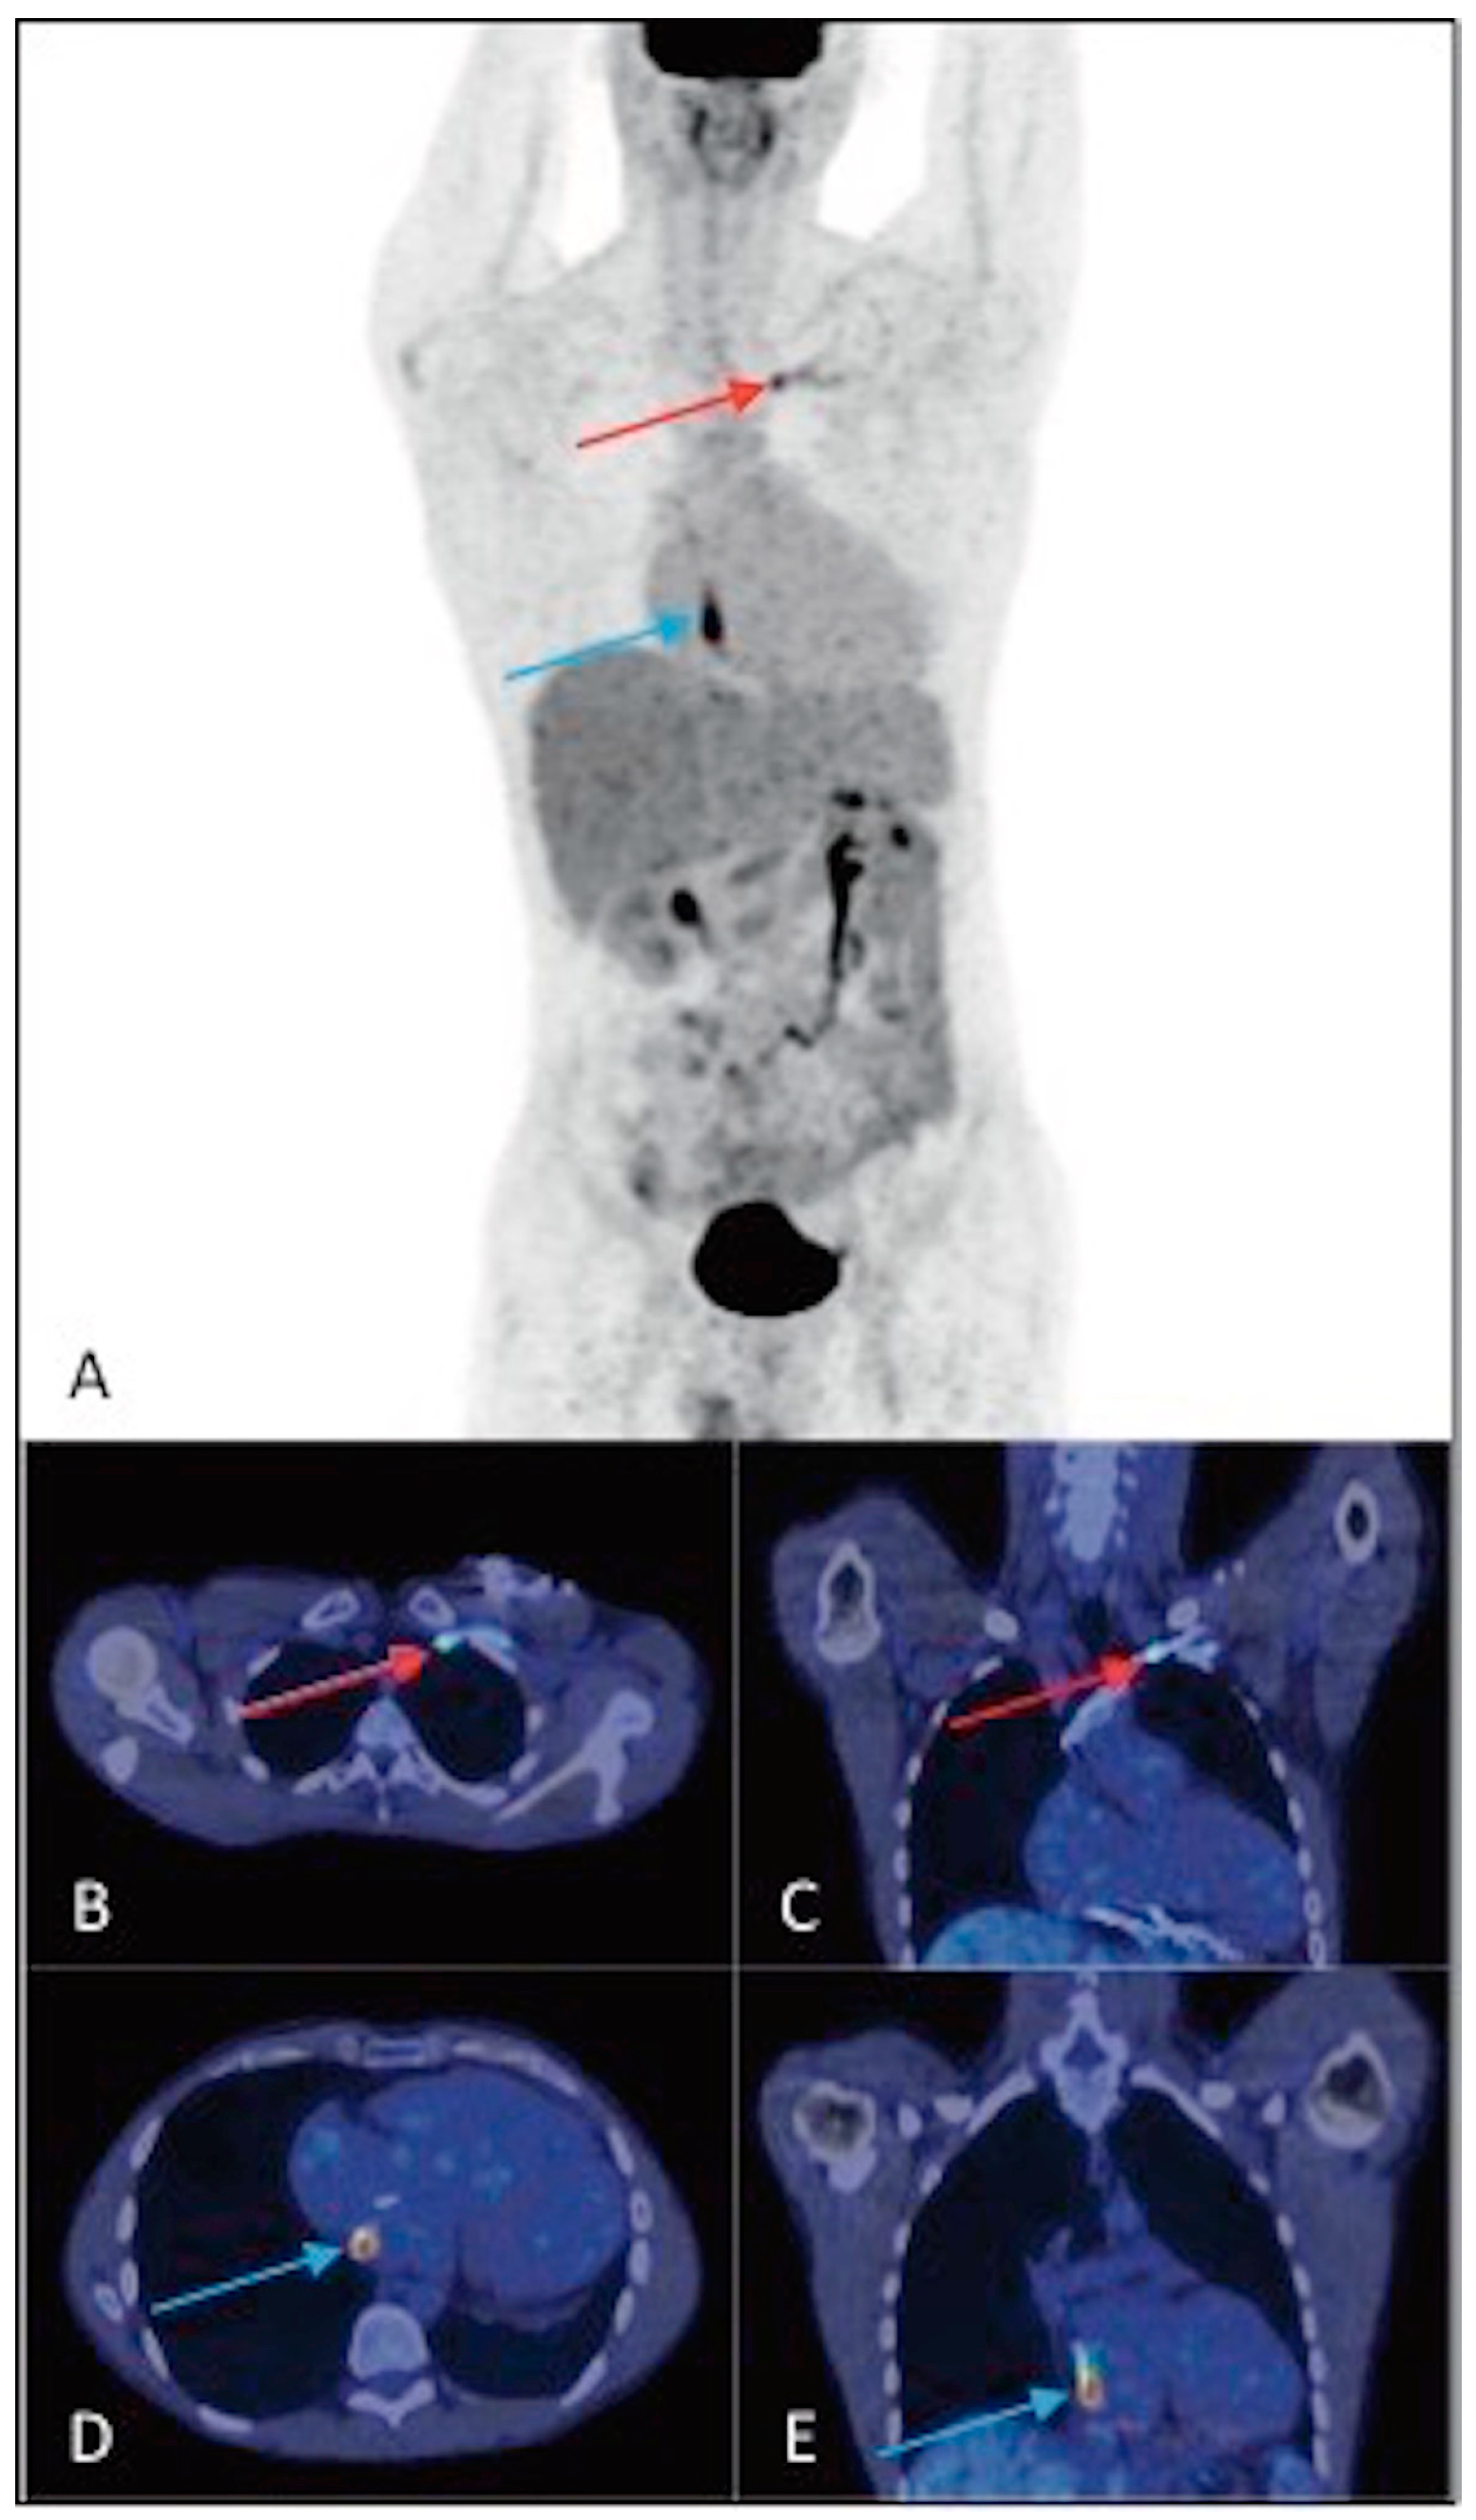

3.2. Results of the 18F-FDG PET/CT Examination Analysis